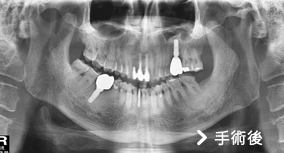

上顎竇增高植牙手術

我們知道,一顆牙齒要屹立不搖,四周要有足夠的齒槽骨去支撐它;同理,「人工植體」也需要足夠的齒槽骨才能在植入後有良好的穩定度。

患者左上第一大臼齒缺牙,齒槽骨高度只剩下3公釐高度,但植牙需要至少10公釐高度的齒槽骨才能建造穩固的植體。

這種狀況下,可依患者狀況評估以「上顎竇增高術」,利用手術器械將「上顎竇膜」分離並提高,並填入骨粉,增加骨頭高度。因為竇膜易破,如傷到破損可能造成的併發症包括:上顎竇膜破裂、鼻竇炎、口腔與鼻竇相通、骨粉或植體感染,因此「上顎竇增高術」屬於較複雜的手術技巧,建議選擇臨床經驗豐富的醫師來操作較為適當。

手術後照片可以明顯看出齒槽骨高度已經增加,確定有足夠骨頭再植入一個植體,也順利替患者解決缺牙所帶來的不便。